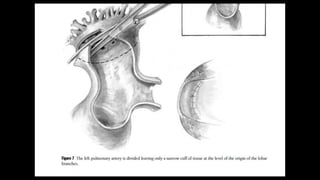

Figure 12-3

A An incision is made into the confluent

portion of the

pulmonary artery. If necessary to achieve

adequate

length, the incision is extended onto the left

pulmonary artery.

B The distal end of a prosthetic valved conduit is shortened to a point just above the heterograft valve. The

conduit shown here is meant to be generic; valves

from a variety of species have been employed. The

composite valved conduit is approximated to the pulmonary artery by continuous suture. To ensure accurate

closure, several suture loops are placed around

the apex of the incision onto the left pulmonary artery

before the prosthesis is pulled into the arteriotomy.

Generous bites of tissue are taken in each stitch,

including as much of the overlying pericardial tissue

as possible to strengthen the anastomosis and ensure

a tight tissue-to-graft approximation. The pulmonary

artery is often thin and fragile, making it extremely

important to use accurate suture technique and follow

the arc of the needle precisely. Low-flow cardiopulmonary bypass or short periods of circulatory arrest,

which reduce the amount of blood in the pulmonary

artery due to aortopulmonary collateral flow, are useful to achieve optimal visualization of the anastomosis.

The suture line is continued in a counterclockwise fashion about halfway around the anastomosis

C The suture line is completed in a clockwise fashion